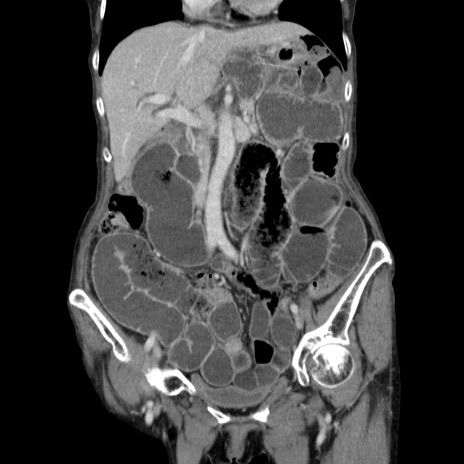

横断像

症例25(冠状断像)

【症例】80歳代女性

【主訴】胸のつかえ感

【現病歴】約9時間前に食後から胸のつかえた感じあり、嘔吐あり、来院。

【既往歴】胃癌(全摘)、胆摘、虫垂炎

【身体所見】心窩部に圧痛あり、反跳痛なし。

【データ】WBC 5700、CRP 0.05